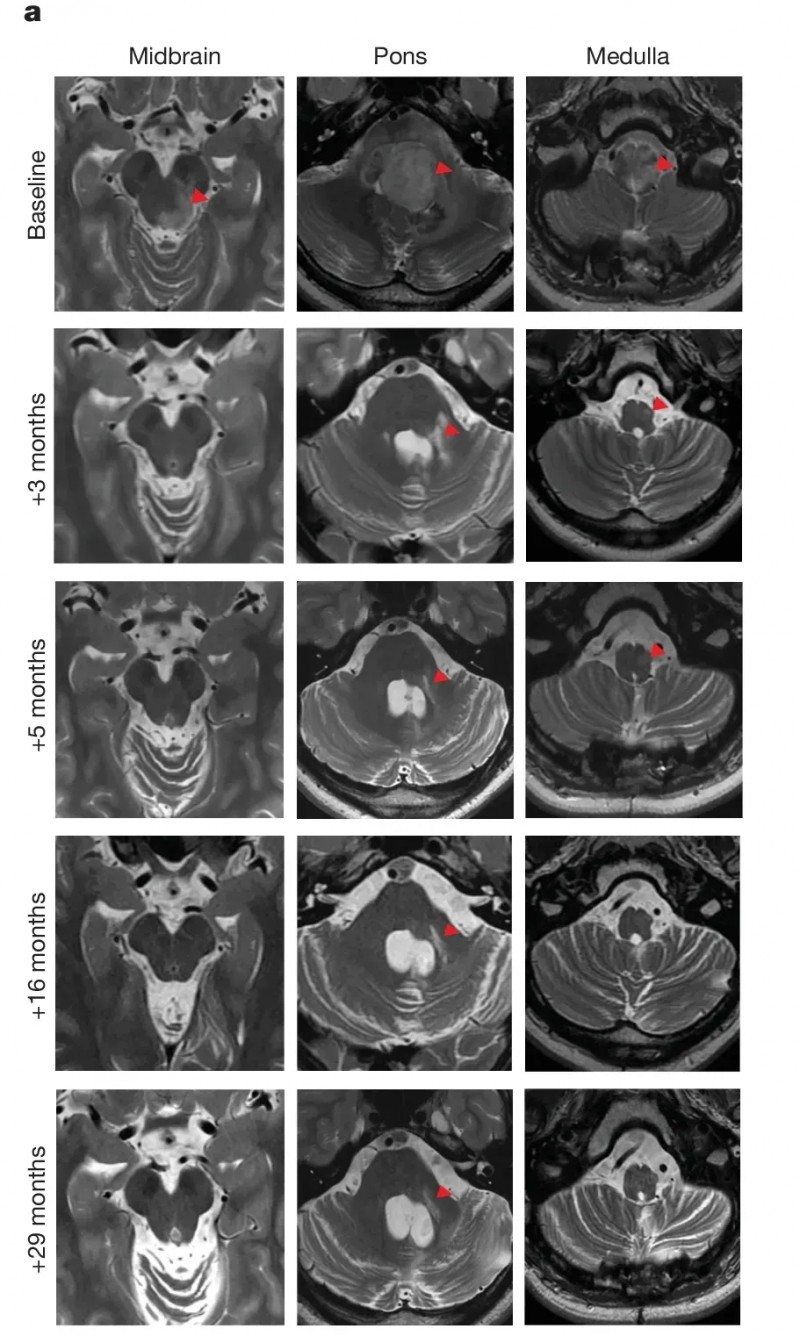

010号患者(DIPG):完全缓解30个月,神经功能大幅恢复

该患者确诊脑桥弥漫性中线神经胶质瘤(DIPG)并完成前期放疗后,影像学提示肿瘤可能进展或假进展。首次输注GD2-CAR-T细胞后数月内,肿瘤持续缩小至完全缓解,且该状态在入组后30个月(数据截止时)仍在持续。治疗前,肿瘤累及中脑、脑桥及延髓,遮挡第四脑室;治疗3个月后,脑干大小恢复正常,周围脑脊液回流改善,大部分脑干T2信号恢复正常,仅脑桥活检道区域残留异常信号,5个月后完全消退(详见下图)。

在临床症状方面,患者入组时存在感觉与运动障碍,需辅助行走(长距离依赖轮椅);治疗后左侧听力、半脸及半身感觉、味觉均明显改善,运动协调性及步态恢复至可独立行走。

▲图源“nature”,版权归原作者所有,如无意中侵犯了知识产权,请联系我们删除